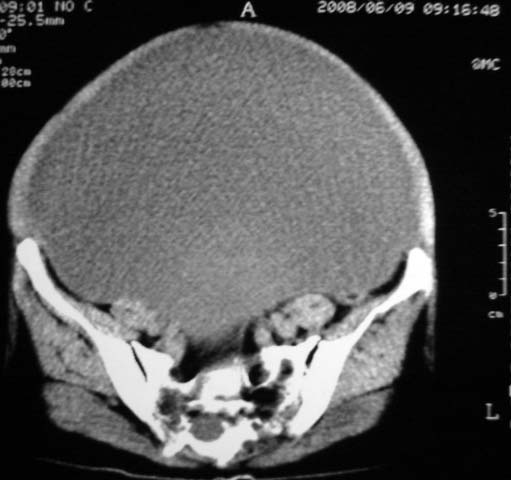

女,75岁,腹部胀大半年余,无其他症状。

考虑来源与卵巢的巨大囊腺瘤或囊肿。

真是腹大如牛,考虑卵巢巨大囊腺瘤或囊肿。

考虑来源于卵巢的巨大囊腺瘤;如果是单纯囊肿不知其前部的更低密度区怎么解释?

考虑来源卵巢巨大黏液性囊腺瘤。